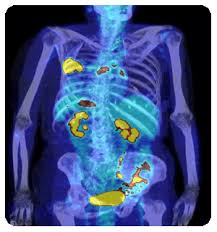

Representantes de entidades médicas defenderam nesta terça-feira, em audiência pública promovida pela Comissão de Seguridade Social e Família, a inclusão do procedimento PET/CT em Oncologia na Tabela Unificada do Sistema Único de Saúde (SUS). Os exames PET (tomografia por emissão de pósitrons) e CT (tomografia computadorizada) são ferramentas padrões de imagens utilizadas para identificar estados de doenças no corpo.

A grande vantagem dessa modalidade de diagnóstico é a capacidade de demonstrar, de maneira eficaz, a presença ou não de câncer, evitando processos invasivos desnecessários.